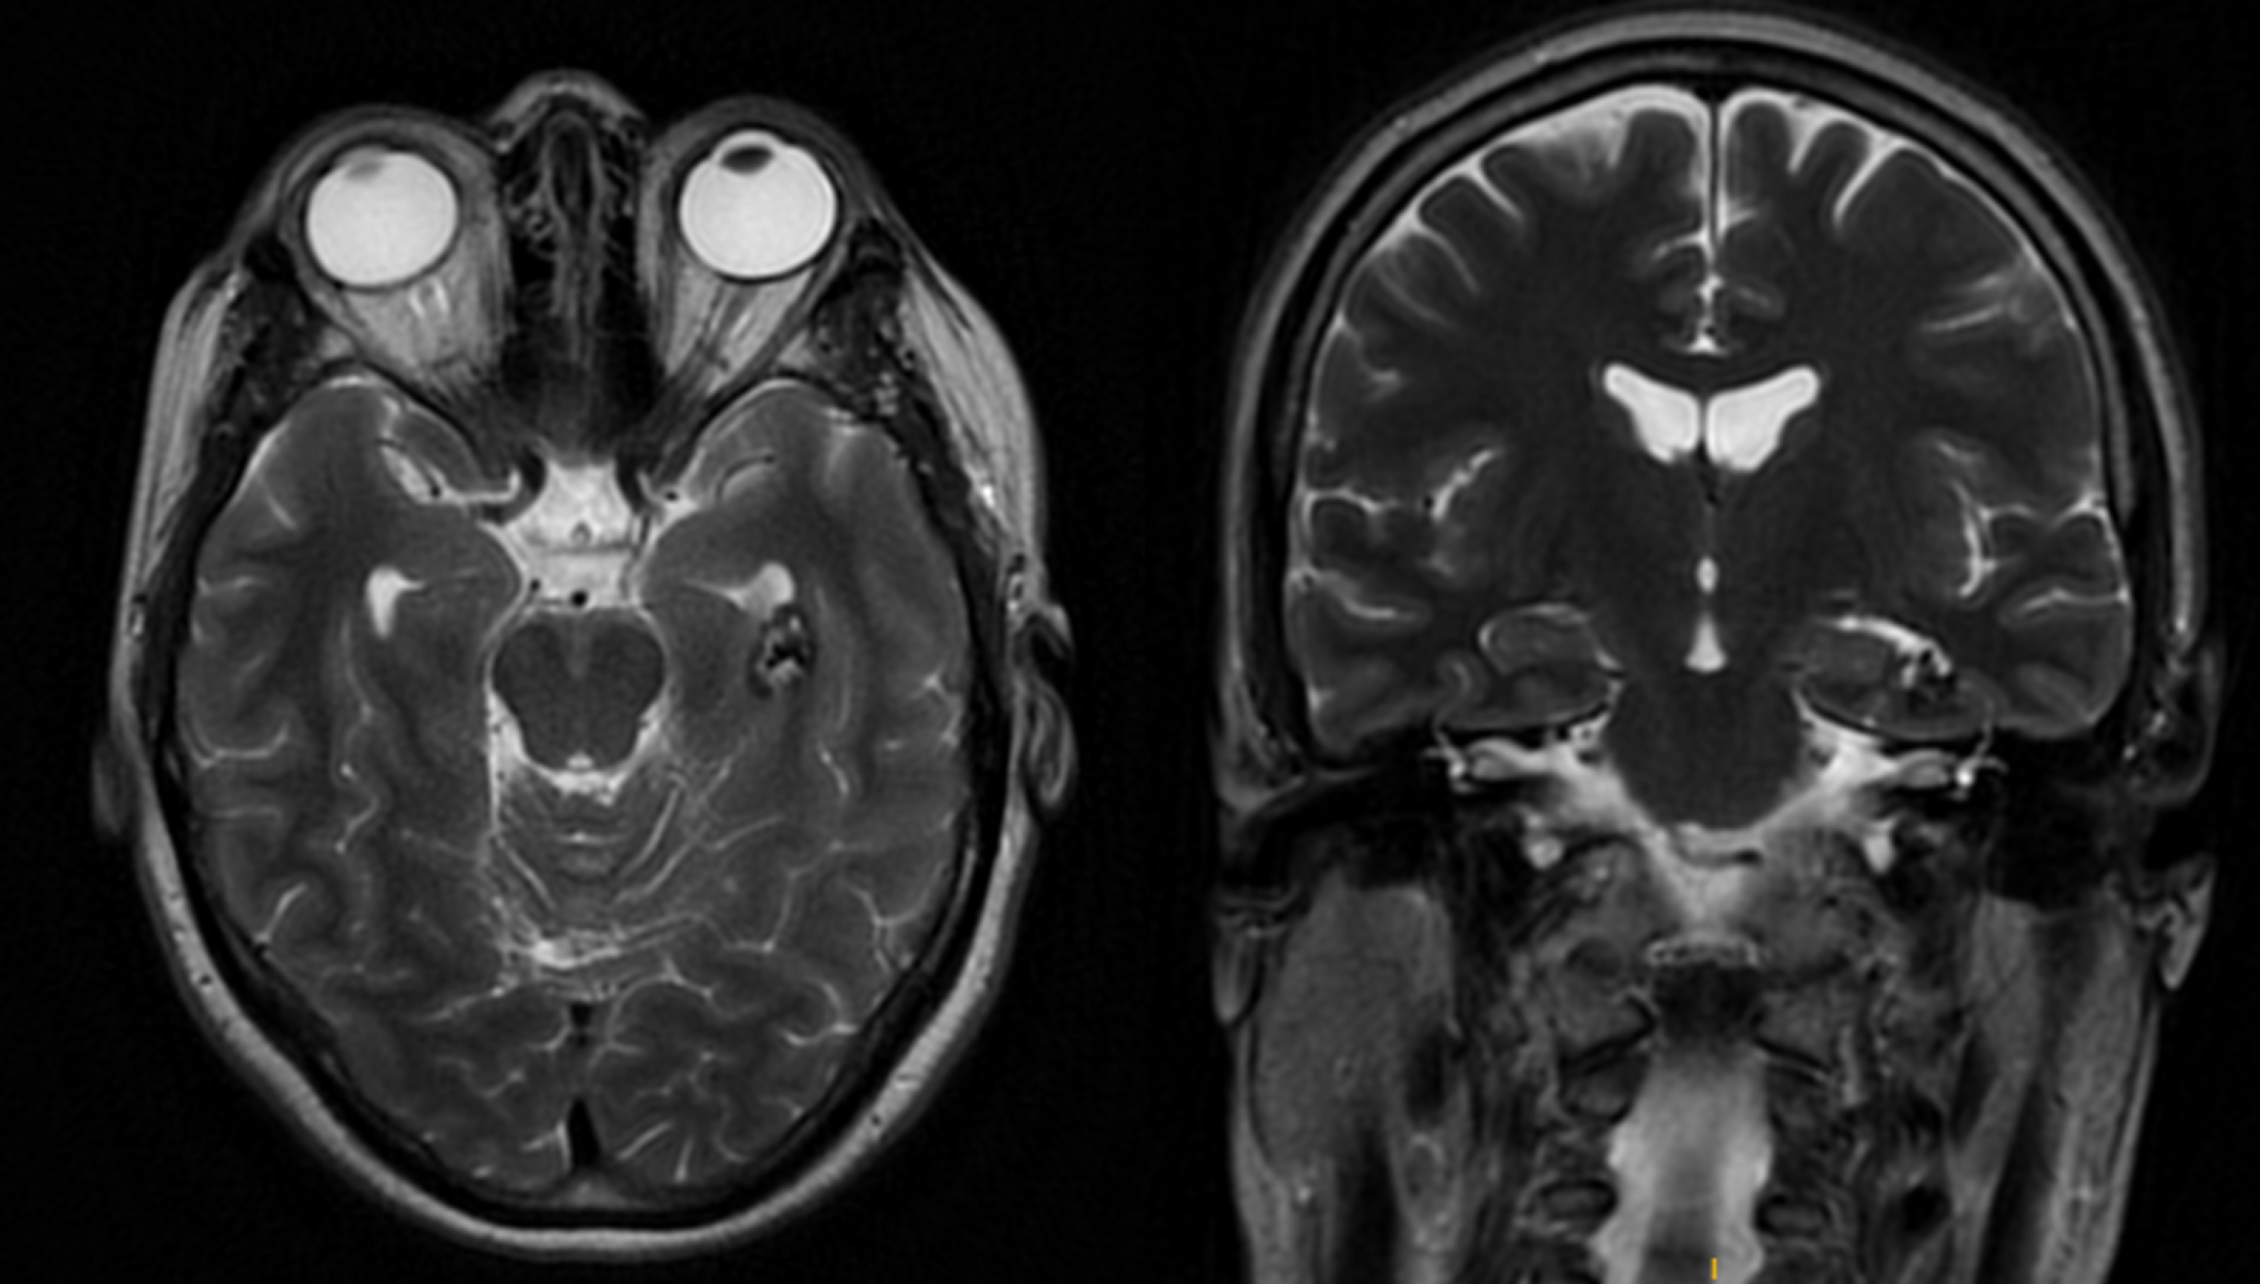

CASO EJEMPLO2: CAVERNOMA INTRA-PARAVENTRICULAR TEMPORAL IZQUIERDO

Fig 1 y 2: Mujer, 48 años, cavernoma incidental.

Fig 3 y 4: Exéresis a través del surco colateral, utilizando un abordaje subtemporal.